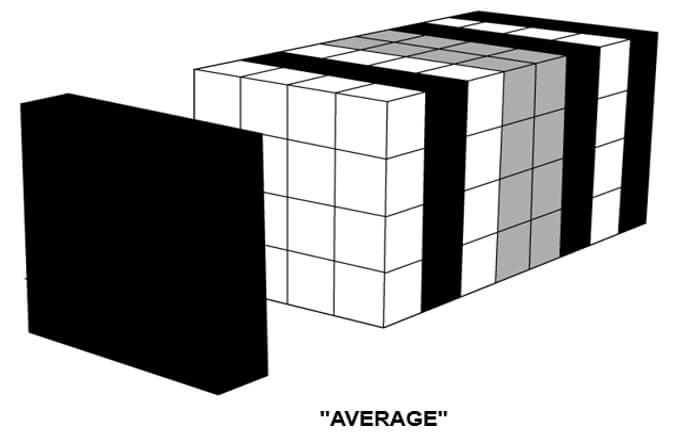

Average

In the average intensity algorithm (AIP), the visualization is averaged. The AIP technique is an algorithm that is intended to create a thick MPR image by using the average of the attenuation through the tissues of interest to calculate the pixel viewed on the computer.